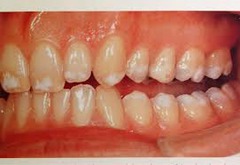

erosion

-loss of tooth structure w/ smooth polished surface -cause: chemical action, bulemia